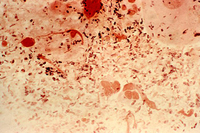

Gonorrhoea infection

Photomicrograph revealing the histopathology in an acute case of gonococcal urethritis using gram-stain technique

US Centers for Disease Control and Prevention/ Joe Millar